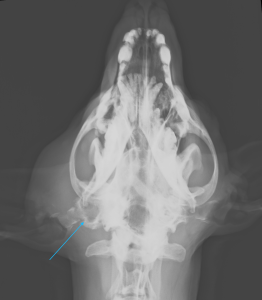

左耳の付け根が大きく腫れ、硬くなっていました。細い針を刺して検査すると菌や白血球が集まっていて、感染が疑われたので抗生物質を内服してもらいました。また、レントゲンでは耳道が石灰化している所見が見られました。

CTでは左耳の耳道、鼓室胞の中に充実性の病変が見られ、耳道の骨は一部融解していました。CTの所見から真珠腫性中耳炎が疑われました。真珠腫は外耳炎などにより鼓膜が破れ、鼓膜の内側の中耳内、鼓室胞に上皮細胞が浸潤することで慢性的に炎症が起こり、痛みや神経症状、開口障害といった症状が出ます。